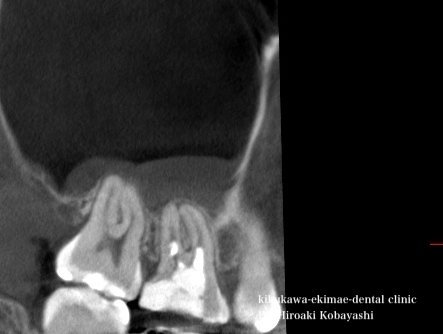

保険での限られた時間では中々、バイ菌を取り切ることは困難です。十分に時間を確保しラバーダム防湿を行い顕微鏡にて前医の取り残している感染源を除去していきます。

2回ほどの根管治療にて、上顎洞炎の病態である粘膜の肥厚も収まり、問題なく治癒しました。